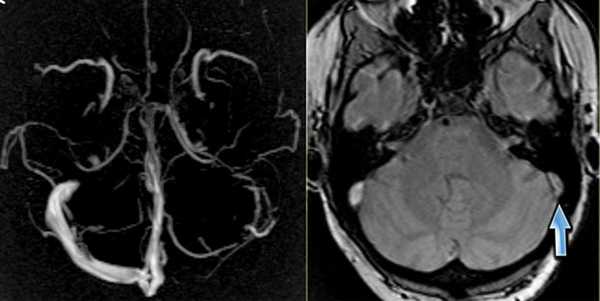

МР-венография - отсутствие визуализации кровотока в правом поперечном синусе и яремной вене.

МР-венография: тромбоз левого поперечного синуса. Отмечается потеря МР-сигнала от левого поперечного синуса.

Наличие визуализации синуса на «сырых» данных или же МРТ головного мозга подтверждает тромбоз синуса и исключает его гипоплазию.

МР-венография: тромбоз правого поперечного синуса. Отмечается потеря МР-сигнала от правого поперечного синуса.

Наличие визуализации синуса на «сырых» данных или же МРТ головного мозга подтверждает тромбоз синуса и исключает его гипо- и аплазию.

Тромбоз правого поперечного синуса. Отсутствие феномена «пустоты потока» от правого поперечного синуса на МРТ головного мозга. Отсутствие визуализации правого поперечного синуса на МР-венографии.